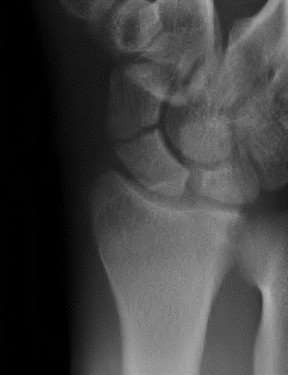

Question 19

A 28-year-old male sustains a closed comminuted tibial shaft fracture.

Two hours post-injury, he develops severe leg pain unyielding to narcotics. His blood pressure is 120/80 mmHg. Intracompartmental pressure monitoring is performed. Based on current guidelines, which measurement dictates an emergent 4-compartment fasciotomy?

Explanation

Acute compartment syndrome is classically defined by tissue hypoperfusion. The absolute compartment pressure is less reliable than the differential pressure (Delta P). A Delta P (Diastolic Blood Pressure minus Compartment Pressure) of less than 30 mmHg is an absolute indication for emergency fasciotomy, as capillary perfusion gradient is lost when tissue pressure approaches the diastolic pressure.